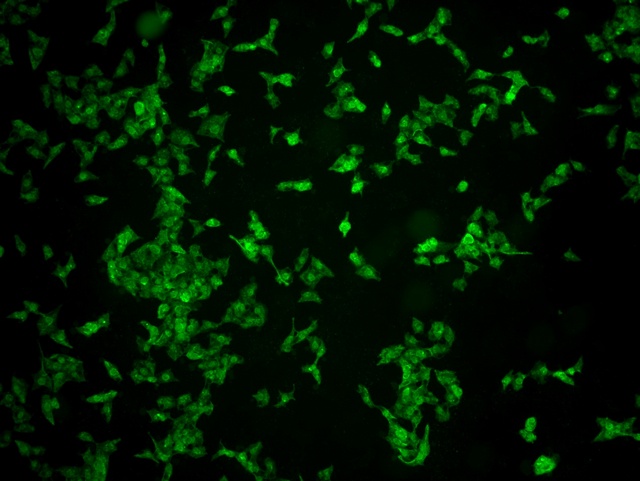

南華大學(xué)在生物醫(yī)學(xué)研究領(lǐng)域一直走在學(xué)術(shù)前沿,近日,該校引進(jìn)Mshot明美的倒置熒光顯微鏡MF52-N,搭配顯微鏡相機(jī)MSX2,為細(xì)胞切片標(biāo)本的研究提供了強(qiáng)大的技術(shù)支持,進(jìn)一步提升了科研實(shí)力。

MF52-N倒置熒光顯微鏡以其數(shù)顯LED熒光模塊和深度優(yōu)化的光路設(shè)計(jì),成為細(xì)胞切片觀察的理想選擇。其簡(jiǎn)單易用的熒光激發(fā)操作,大大降低了實(shí)驗(yàn)難度,提升了工作效率。同時(shí),該顯微鏡還能提供高質(zhì)量的相襯、熒光和明場(chǎng)成像,確保科研人員能夠捕捉到細(xì)胞切片的每一個(gè)細(xì)節(jié)。

在南華大學(xué)的實(shí)驗(yàn)室中,科研人員正借助這套先進(jìn)的顯微系統(tǒng),對(duì)細(xì)胞切片標(biāo)本進(jìn)行深入探索。

此外,MSX2顯微鏡相機(jī)的加入,更是如虎添翼。這款相機(jī)以其高分辨率和敏銳的圖像捕捉能力,記錄了實(shí)驗(yàn)過(guò)程中的每一個(gè)重要瞬間,為數(shù)據(jù)分析與論文發(fā)表提供了有力支持。